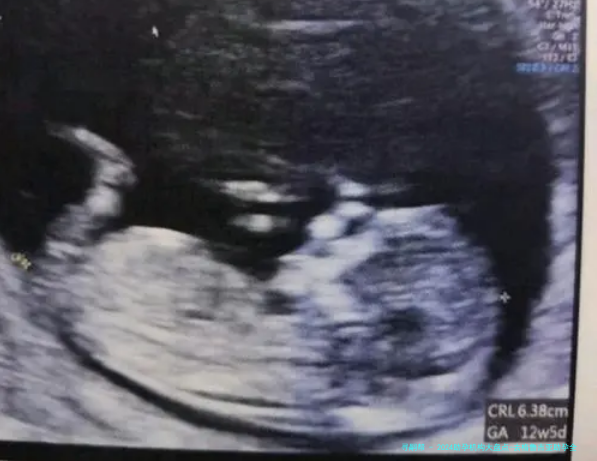

| 在格鲁吉亚医疗与待产阶段(约6-12个月) | 完成医疗步骤(促排卵、取卵/取精、胚胎培养与移植)、通过医疗学形式认定妊娠成功、孕期观测。 | 医疗流程需遵照医生的一对一引导;建议留存备用应急资金以应对可能的额外医疗花费。 |